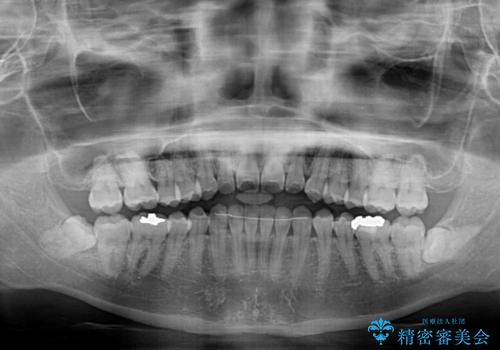

前歯のクロスバイト インビザラインによる矯正治療

- 前歯のクロスバイトとデコボコを気にして来院された患者様です。

骨格的に下顎前突傾向であるため、自己管理が煩わしくないようであれば、インビザラインによる矯正治療がお勧めとなります。

インビザラインを用い、下顎歯列を後方に移動させながら全市の被蓋を改善し、歯並びを整えていくこととしました。

途中マウスピースが使用できず、来院されない期間があり、治療期間は長くかかりましたが、無事に治療を終えることができました。